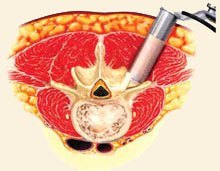

The muscles surrounding the spine will then be dilated to allow access to the section of spine to be stabilized. After the spine is accessed, the lamina (the “roof” of the vertebra) is removed to allow visualization of the nerve roots. The facet joints, which are directly over the nerve roots, may be trimmed to give the nerve roots more room.

Bone Graft Material Placement

The nerve roots are then moved to one side and the disc material removed from the front (anterior) of the spine. A bone graft is then inserted into the disc space. The bone graft material acts as a bridge, or scaffold, on which new bone can grow. Screws and rods are inserted to stabilize the spine while the treated area heals and fusion occurs, and the ultimate goal of the procedure is to restore spinal stability.